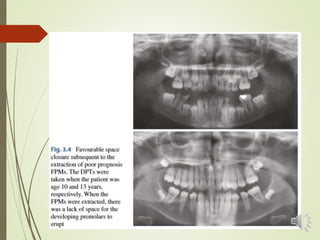

 The ideal time to extract 6s to encourage complete space

closure through the mesial migration of the 7s is generally

considered to be represented by the onset of the

calcification of the furcation of the roots of the unerupted L

7s (8–10 years).

 Other factors to consider are the presence of the

developing 8 and the mesial angulation of the 7.